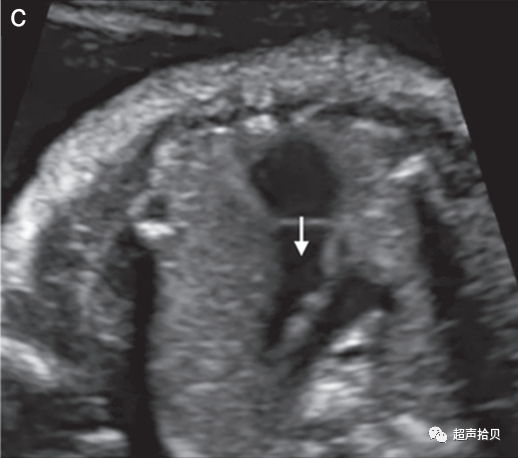

1. 胎儿颜面部的评估应包括冠状面(正面)显示上唇,以评价有无唇裂畸形唇裂(图3a);

2. 如果技术上可行,还包括正中矢状面(图3b);

3. 应该检查眼眶的存在和正常的位置以及眼睛的距离(图3c);

图3胎儿颜面部的超声图。

(a)口腔、嘴唇和鼻子通常通过冠状面进行评估。

(b)如果技术上可行,应获得面部中矢状面,因为它为双侧唇裂、前额凸起、小颌畸形和鼻骨异常提供了重要的诊断线索。(请注意,鼻骨检查是可选的)

(c)两个胎儿眼眶应呈现对称和完整,眼睛间距约为一个眼眶的直径。